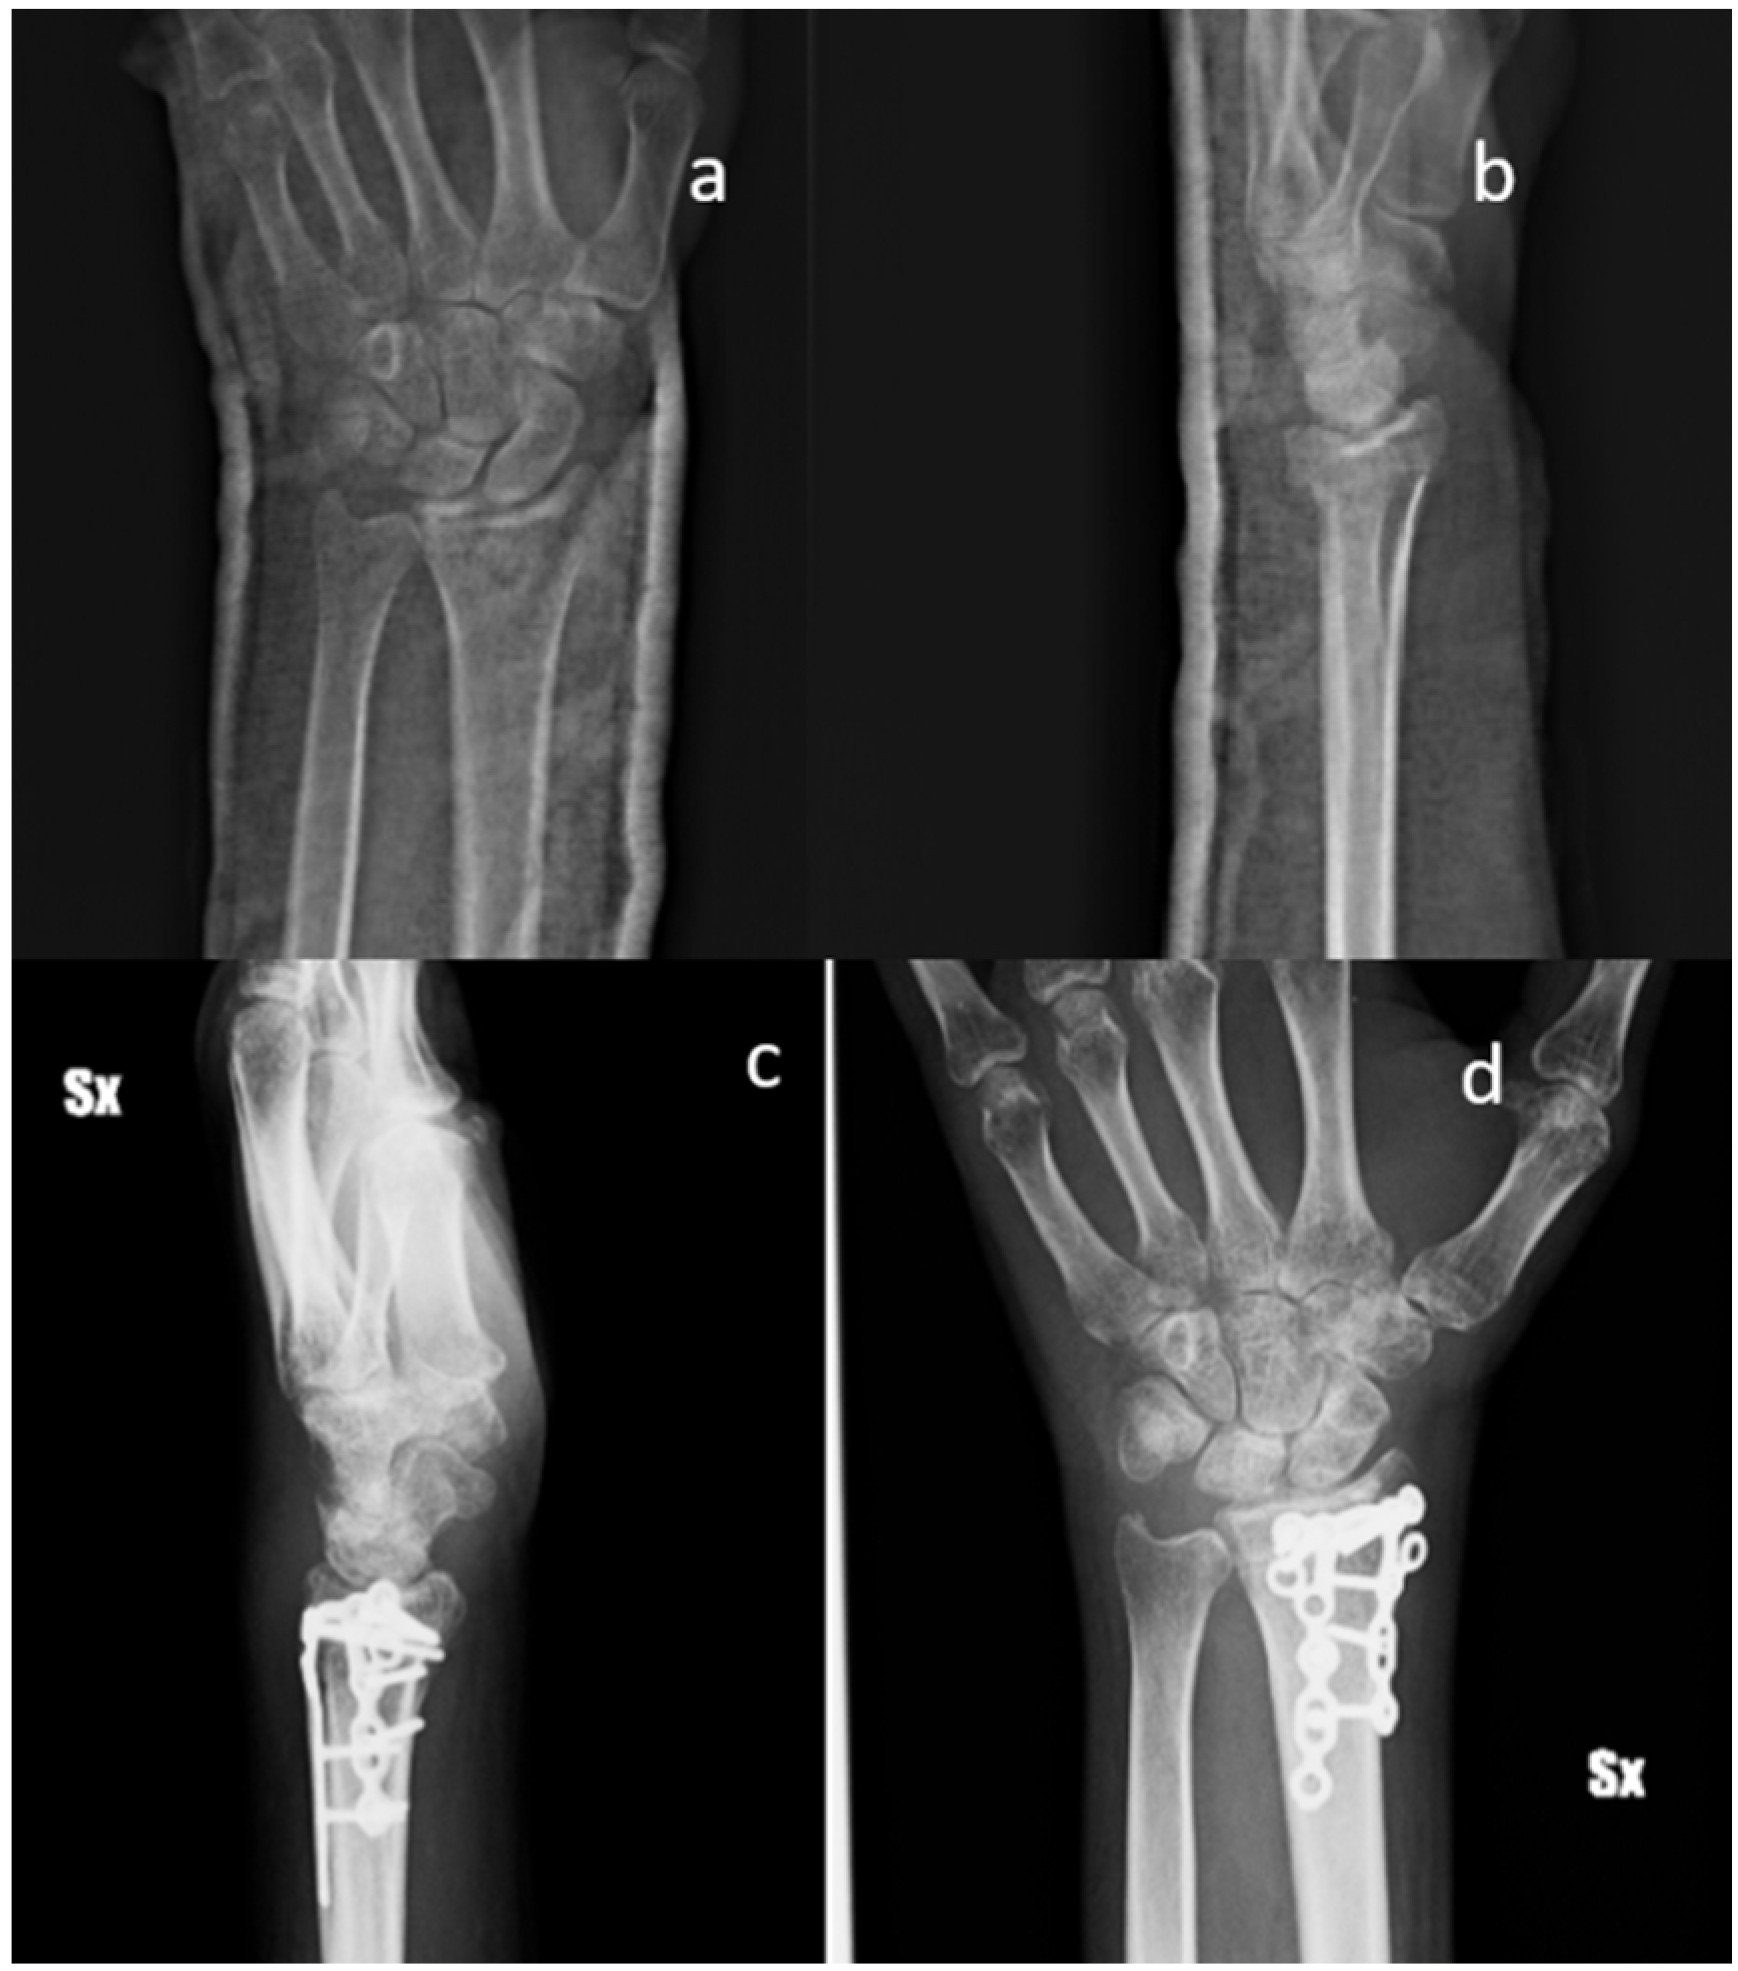

Figure 3.

Standard X-ray of a displaced articular fracture of the distal radius associated with styloid ulna fracture. Preoperative images in AP (a) and Lateral (b) view are compared to post-operative X Ray at five months (c,d). The images show callus formation and remodeling of the smart bone. (Male, 50 yy).

All the patients performed radiographic examinations during regular follow-up. Radiographs were examined for callus formation, bone resorption, implant stability, and SB integration [28] (Figure 1, Figure 2 and Figure 3).

X-ray images of 7 out of 19 patients showed that fractures were consolidated at two months: the radiographic controls, indeed, showed abundant callus formation. An exemplificative case is presented in Figure 2. The remaining 12 patients showed reduced callus formation after two months and performed an additional X-ray imaging check at five months after surgery (exemplificative case shown in Figure 3). In all cases, radiolucency of the xenografts was assessed, which became progressively more similar to that of the surrounding healthy bone tissue.